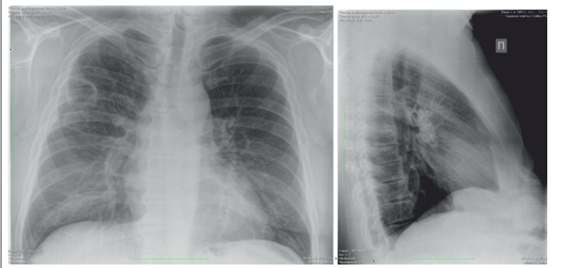

При рентгенографии органов грудной клетки 10.06.2016 г. в двух проекциях определяется наличие двух полостей в верхней доле справа (2,5×2,5 мм и 3,5×3,5 мм) без уровня жидкости с тонкими стенками (рис. 2). Слева легочные поля без патологии.

рис.2